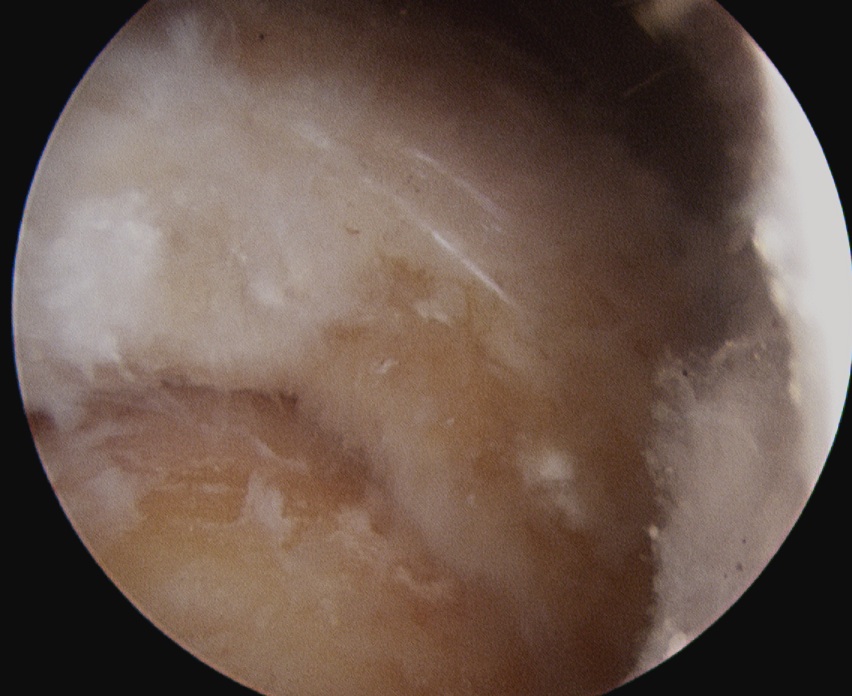

Calcium NoduleCalcium Needle

Location of calcium deposit under vision and with needle